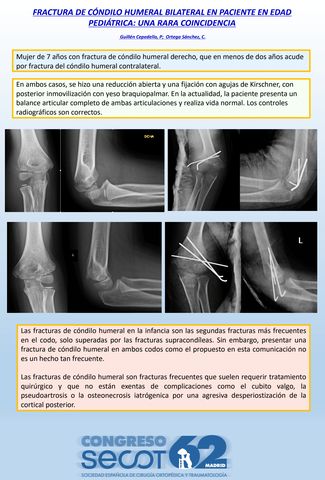

¿TIENE SENTIDO LA PATELECTOMÍA EN FRACTURAS CONMINUTAS DE RÓTULA EN LA INFANCIA?

MARÍA DEL PILAR RODRÍGUEZ SANGUINO, GUILLERMO SOSA GONZÁLEZ, ALMUDENA SCOLA TORRES, MARÍA DEL CARMEN BORGES CARCAMO, ANGEL JOSE VILLA GARCIA